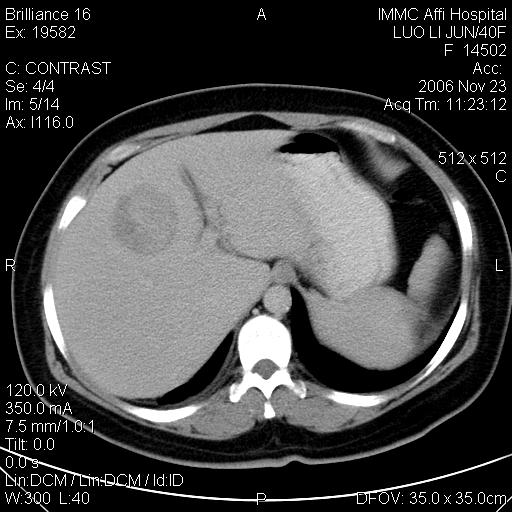

标题: CT5664:我也发一个肝脏的片子大家看看

很典型的肝癌。

速升速降,典型肝癌.

是啊,典型的早出早归!

快进快出典型肝癌.

符合肝癌的增强特征。支持肝癌!

病灶好圆!可能恶性度不高。

不能除外肝细胞腺瘤吧,还是得结合病史。

很好的片子,可惜增强做的比较失败,a期时间没有把我好,实际到了静脉早期了,否则会更典型。

最终考虑是肝腺瘤